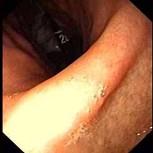

问题 女,36岁,上腹痛2年,伴嗳气、呃逆,弯腰时加重,查体未见特殊。胃镜如图,钡餐未:可见左侧隔上囊状阴影。最可能的诊断是 ( )

选项 A、幽门梗阻 B、反流性食管炎 C、胆石症 D、消化性溃疡 E、食管裂孔疝

答案 E